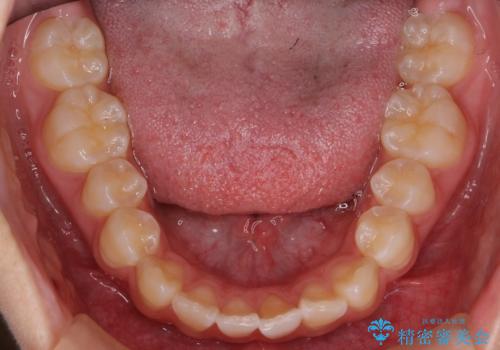

出っ歯 軽度のがたつき インビザラインで

- 20代女性

- インビザライン

- 奥歯を後ろに下げる処置をおこなっています。

前歯にオープンバイト気味の症状がありましたが、前歯を後ろに下げることでしっかりかませています。